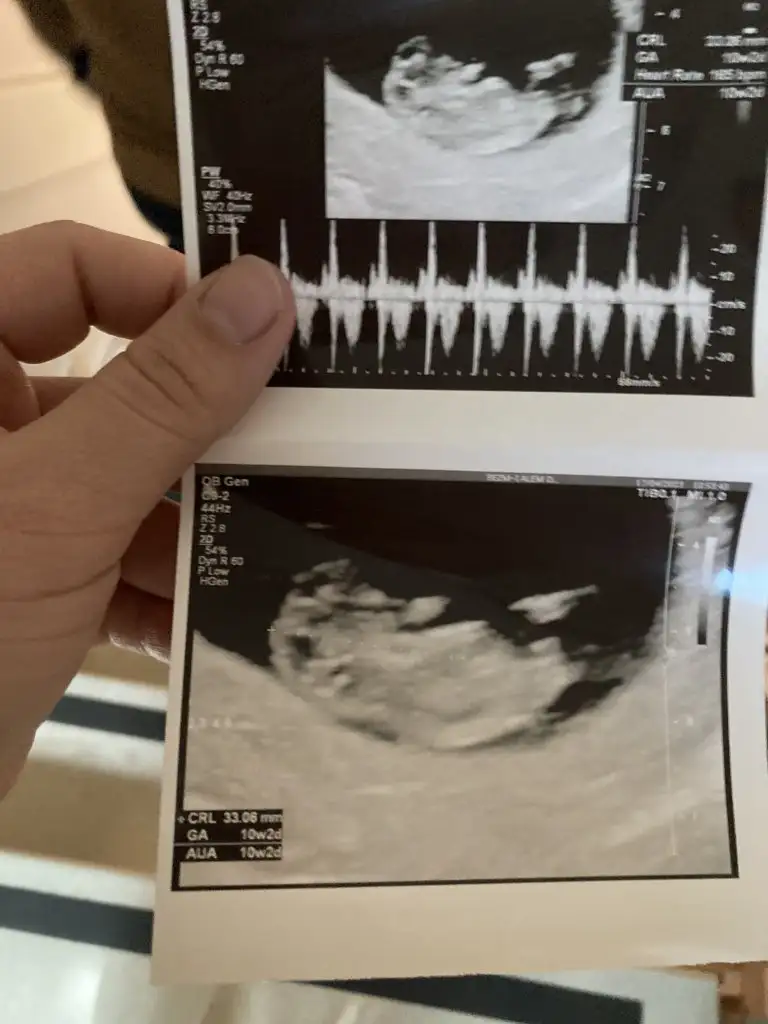

Merhaba, sorununuzu tam bilmiyorum tabii ama bende de bacak krampları ve ayağımda tendon çekilmesi vardı, doktorun önerdiği magnezyum takviyesi iyi geldi. Arada spor salonunda bacak çalışmışım gibi ağrıyor hala bir saat yürüsem ama magnezyum bayağı iyi geldi.Selamlaaar bizde kontrolden geldikçe şükür iyiyiz herşey yolundahaftasıyla uyumlu 10+2 yiz.ki hafta sonra ikili teste gideceğim . Bacak ağrımı söyledim şimdi böyle olmasını beklemeyiz ileriki haftalarda olağan birşeymiş bu. Ben de varisim olduğundan bahsedince o zaman 4-5 aylıkken bi kalp damara görünmemi istedi. Gerek görürse kalp damar doktoru 33 haftada kan sulandırıcı kullanabilirmişim önlem amaçlı. Ve ilişkiyi sordum ben yasak koymadıkça devam edebilirsiniz ama bi lekenle kanama olduğu takdirde ikş hafta yasak dedi. Ayda bir iki olabilir dedi sıklığını azaltmamız lazımmış. Böyle işte